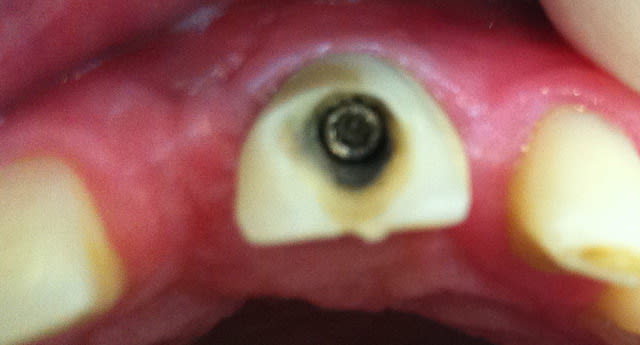

voila un patient que je récupère.. il a une couronne provisoire sur nobel speedy groovy RP en place depuis 2009. Je dois faire la definitive en gerant la position de l'implant (je pense à une fausse gencive).

Petit problème.. le pas de vis n'accroche plus.. quid???